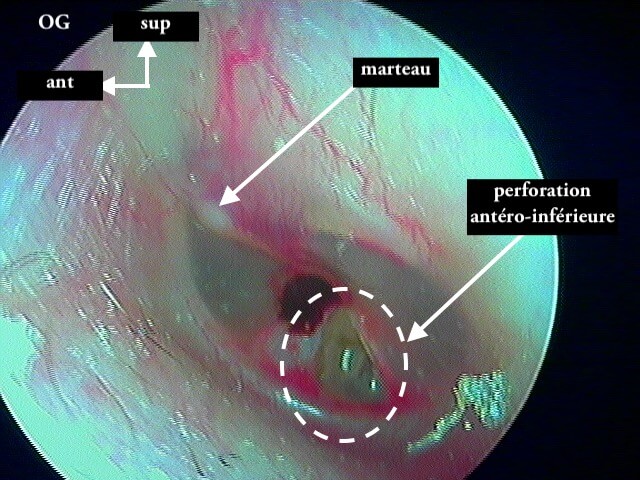

Ici une otite séromuqueuse gauche perforée cicatrisée à 1 mois (cicatrice inférieure)